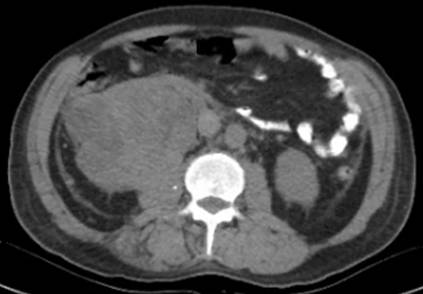

La tomografía simple y contrastada revela trombo tumoral a nivel auricular derecho, con extensión al ostium de la vena renal derecha (figura 1), sin presencia de lesiones metastásica pulmonares, ni hepáticas, sin ectasia de la vía biliar, revela además la presencia de un tumor renal derecho de 15 cm, con 15 UH en fase simple y 59 UH en fase arterial (figuras 2, 3 y 4). El ecocardiograma transesofágico demostró presencia de trombo tumoral en aurícula derecha del 95% de la luz de ésta (figura 5).

Figura 2 Tomografía simple y contrastada que demuestra defecto de llenado a nivel auricular, trombo a nivel de la vena cava inferior, vena renal y tumor renal derecho.

Con los estudios de extensión se establece el diagnóstico de tumor renal derecho cT3c N0 M0, con trombo tumoral Neves IV, así como síndrome de Stauffer. El paciente recibió valoración por medicina interna debido a la hiperglucemia, hiponatremia e hiperazoemia; manejado medicamente con insulina ultrarapida y basal, además con reposición hidroelectrolítica. Se decide someter a tratamiento quirúrgico, el cual consistió en la realización de una nefrectomía radical derecha, resección de trombo de la vena cava inferior a través de venotomía, con abordaje de tipo Chevron y resección intracavitaria de trombo auricular mediante atriotomía a través de esternotomía y by pass cardiopulmonar (figuras 6 y 7). Presentó un sangrado transoperatorio de 2000 ml, requirió trasfusión de 10 concentrados eritrocitarios, 4 plasmas frescos congelados y 4 aféresis plaquetarias, con un tiempo de bomba de circulación extracorpórea de 1 hora y 20 minutos.